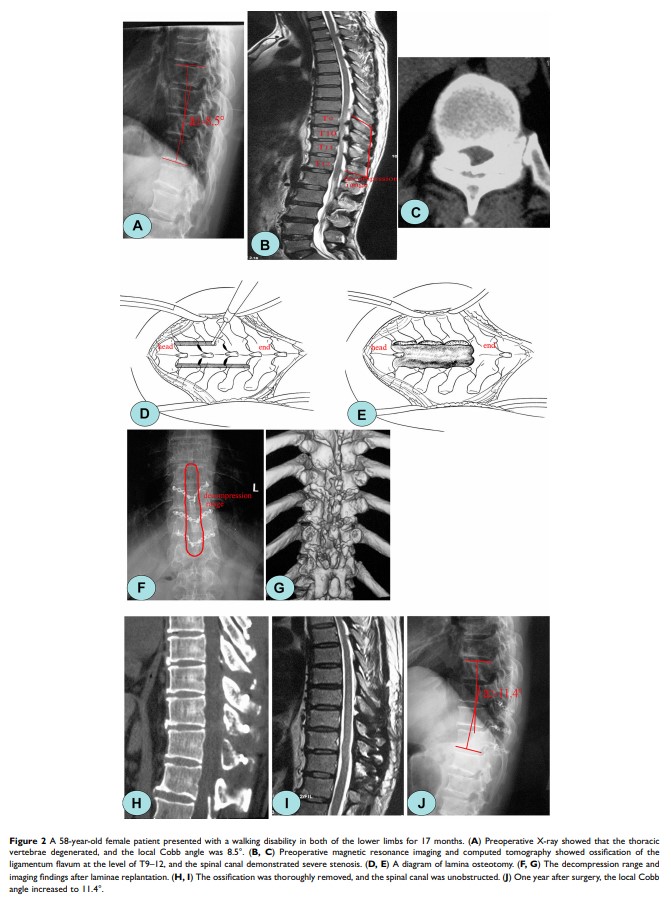

使用椎弓根螺钉固定的椎板分段切除术治疗胸椎黄韧带骨化:椎板截骨术和植骨技术的比较分析